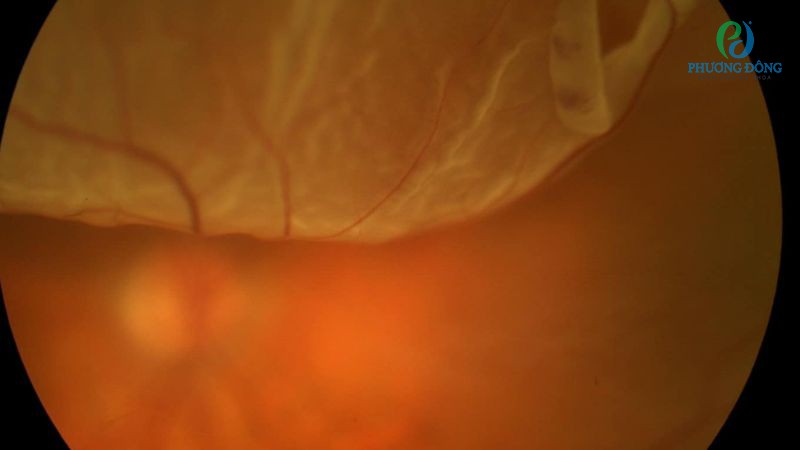

Nếp gấp hình thành cố định trên tất cả các phần võng mạc, khiến võng mạc bong ra có hình dạng giống chiếc ô. Tuỳ theo mức độ mở ô mà sẽ được chia thành 3 loại như sau:

- D1: Ô vẫn mở rộng.

- D2: Ô hẹp nhưng vẫn quan sát rõ đĩa thị.

- D3: Ô đóng hoàn toàn, không nhìn thấy đĩa thị.